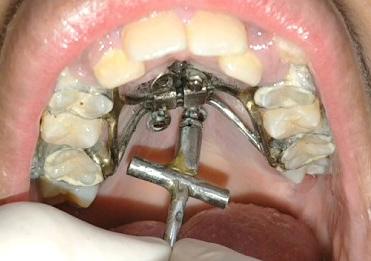

Panoramic radiogram revealed a late mixed dentition with un-erupted wisdom teeth and second molars. A significant finding was noted in that the maxillary cuspids were in transposition with the lateral incisors. There was excellent bone support and no sign of periodontal or peri-apical pathology (Figure 2-A).

Lateral Cephalometric radiogram revealed a narrow airway in the tonsil area (5.0 mm), retrognathic maxilla and mandible (SNA - 78°, SNB - 76°), retrusive maxillary incisors (U1/SN - 91°), retrusive mandibular incisors (L1/GoM - 83°). She was Class III skeletally as ANB, Wits and the Harvold ∆ were – 2.4°, -5.0 mm and 24.8 mm The patient was hyper-divergent as seen from NS/GoM of40° and a Lower gonial angle of 79.7°. The patient was in CVMS 2 - 3 (Cervical Vertebrae Maturation Stage) (Figure 2-B) and an A-P Radiogram revealed a posterior crossbite (Figure 2-C).

Figure 2A: Pre-treatment, Panoramic radiogram Figure 2B: Pre-treatment, lateral Cephalometric radiogram

Figure 2C: Pre-treatment, AP Cephalometric radiogram

A Bolton tooth size discrepancy analysis could not be evaluated because the cuspids were not yet erupted. It was noted that the partially erupted maxillary lateral incisors exhibited some signs of microdontia as they appeared to be narrow compared to the upper central incisors.